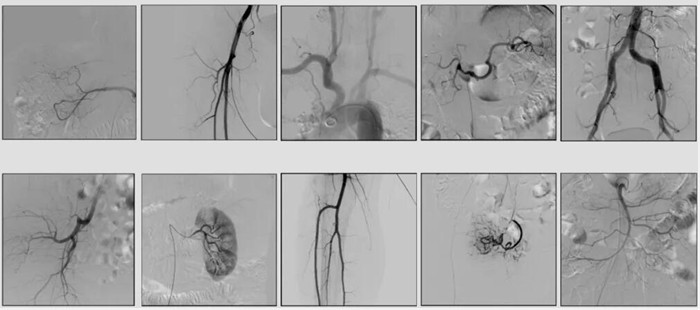

2)中C,學(xué)名外周介入C形臂(Peripheral Interventional C-Arm)。與小C相比,中C不僅大幅提高了X射線系統(tǒng)功率,更重要的是增加了減影等血管機相關(guān)功能,基本可以完成80%的介入手術(shù)需求,主要應(yīng)用在周圍血管科、消化內(nèi)科、婦科、整形科等領(lǐng)域。

中C在周圍血管領(lǐng)域有重要價值